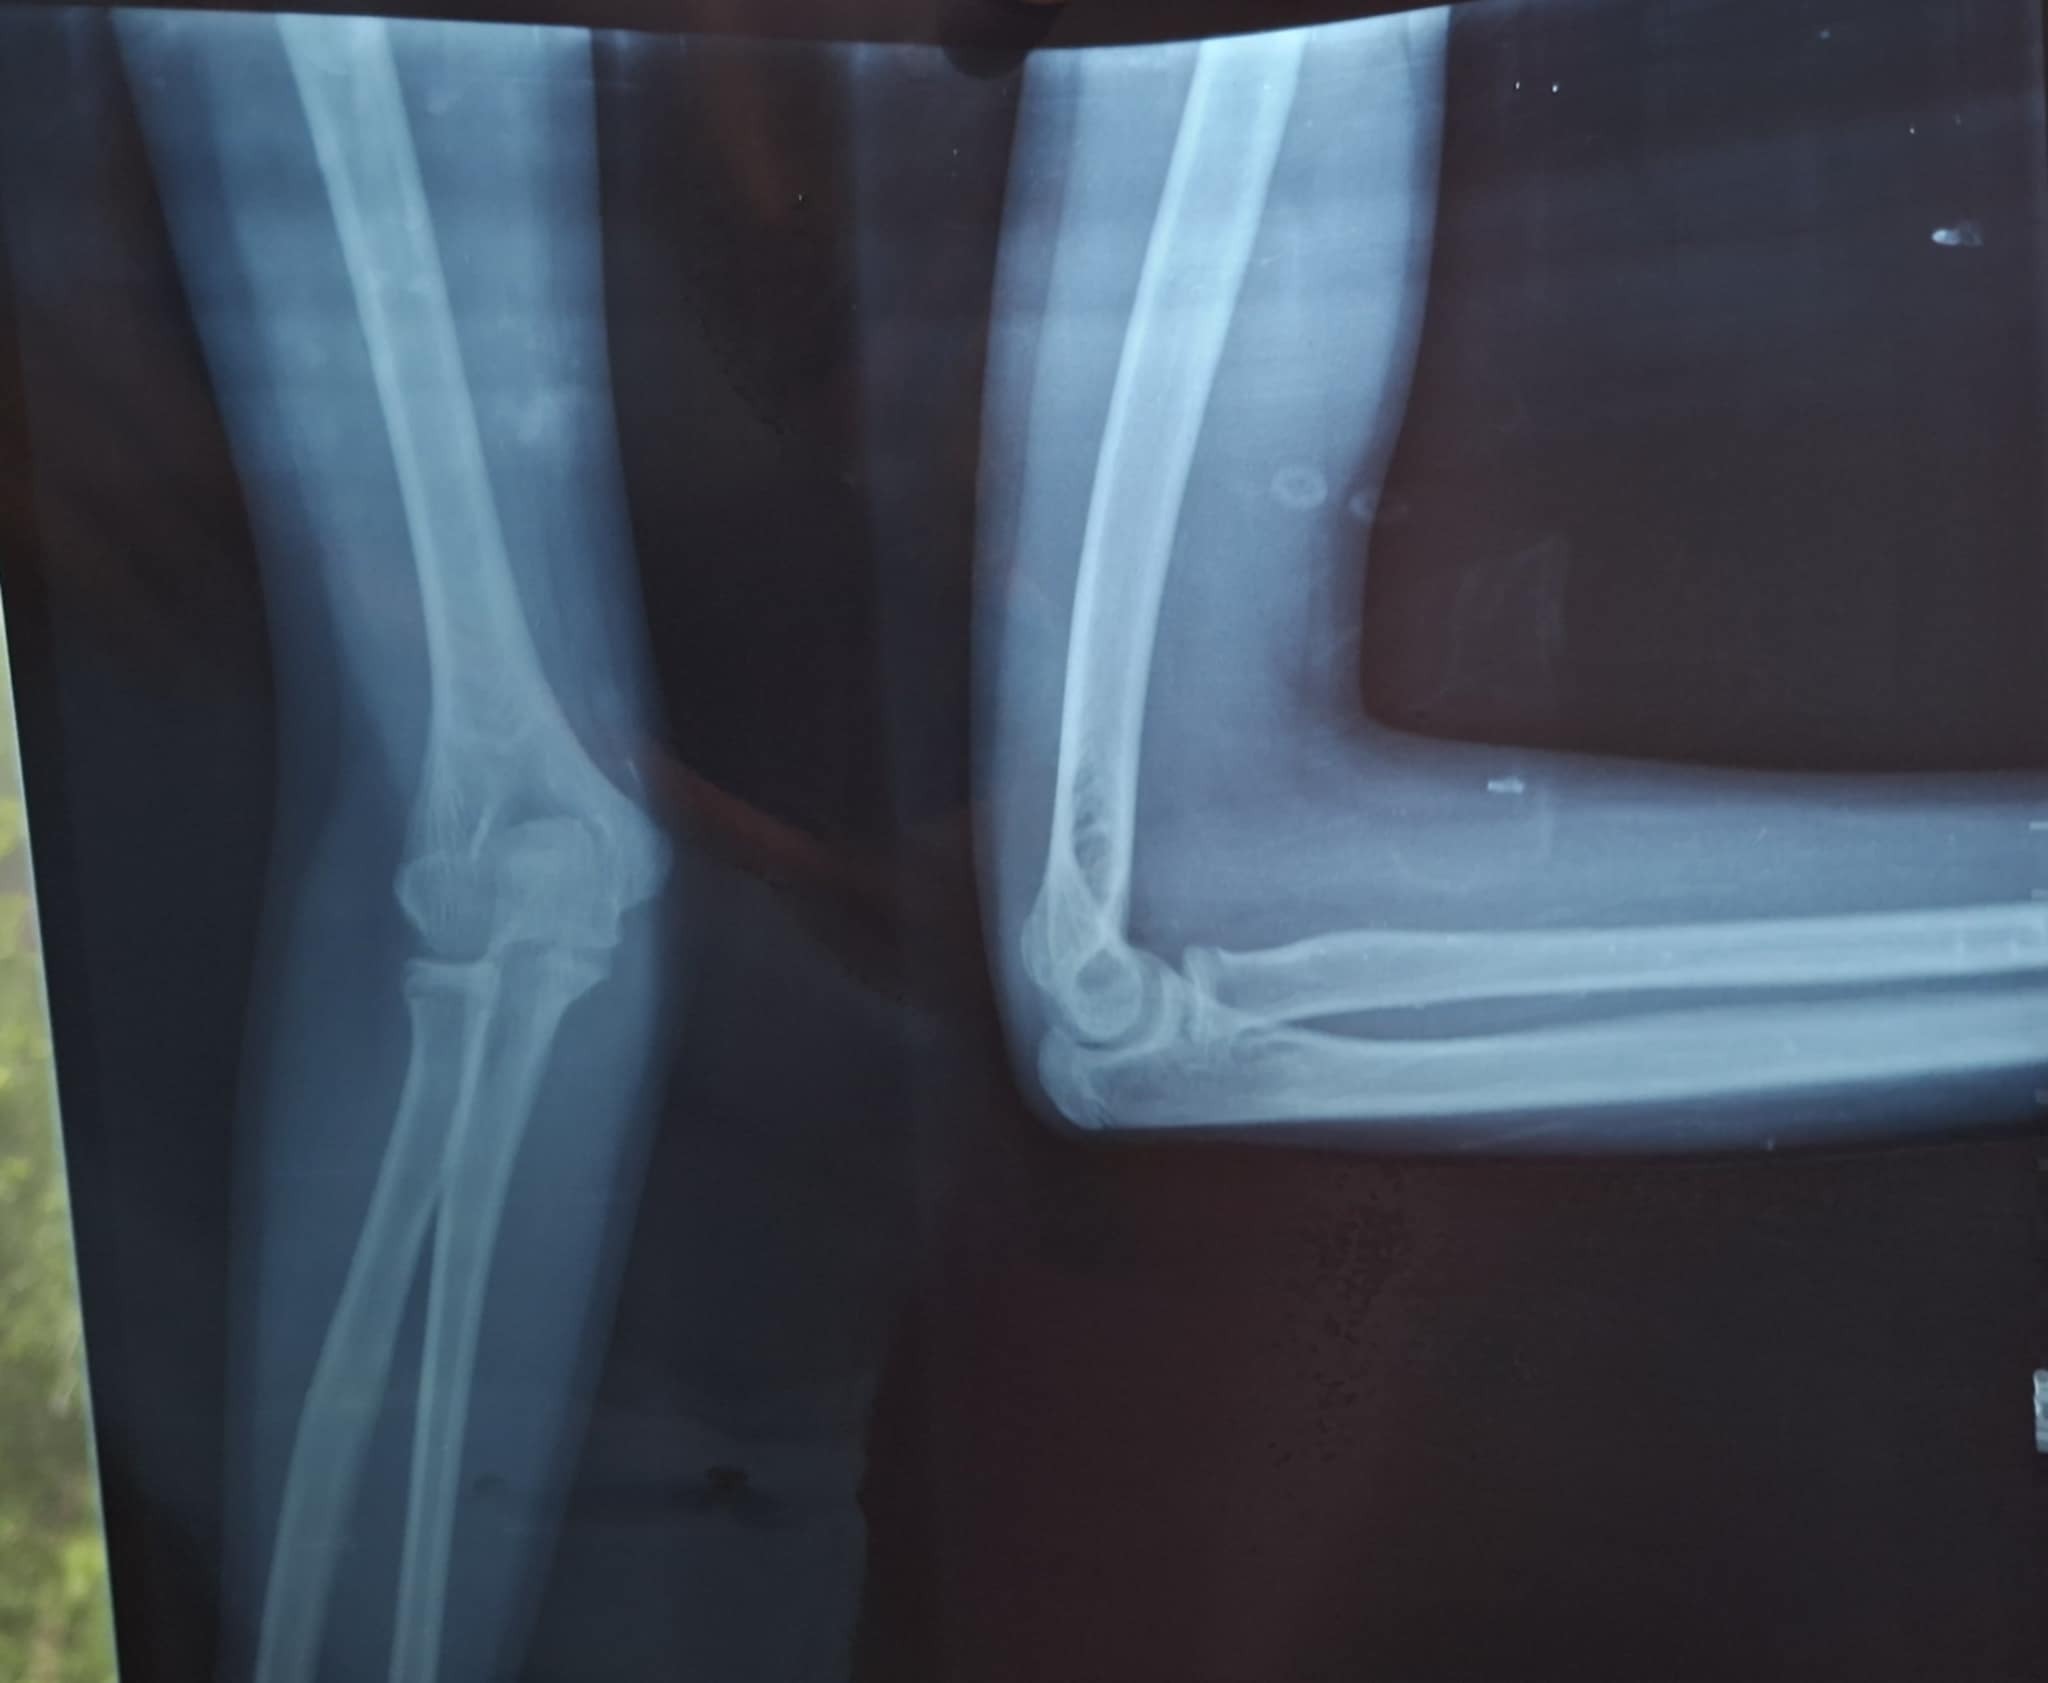

बिहीबार राति तीजको नाँच हेरेर फर्किदै गरेका एकै उमेर समूहका तीन-चार जना बालिकालाई लक्षित गरी आराेपितहरुले लखेटे । लखेट्दा भेटाउन नसकेपछि पछिल्तिरबाट ढुङ्गा हाने, ढुङ्गाले १३ वर्षीया ती बालिकाकाे दाहिने पाखुरामा चाेट लाग्याे उनी ढलिन् तर उनका साथीहरु भागेर जाेगिए ।

बालिकाकाे दाहिने हात मर्केकाे, गुप्ताङ्गमा घाउ हुनुसंगै रक्तश्राव भइरहेकाे दैलेख अस्पतालकाे एकद्वार संकट व्यवस्थापन (ओसीएमसी)का स्वास्थ्यकर्मी तथा मामिला व्यवस्थापक समूहले जानकारी दिएकाे छ । बालिकाकाे स्वास्थ्य सुधार भए पनि नियमित अस्पतालकाे रेखदेखमा रहन सल्लाह दिइएकाे छ ।